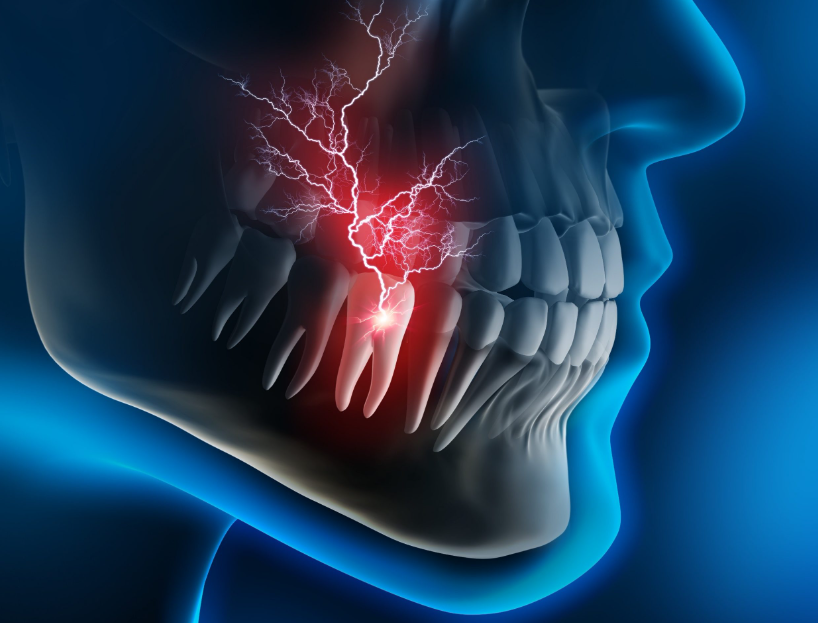

As humans have evolved, our jaws have become smaller. Due to this, there is often not enough space for the wisdom teeth to emerge properly. As a result, they may erupt at an angle or remain impacted (trapped beneath the gums). When they grow at an angle, it’s difficult to clean the area properly, leading to food accumulation. This can cause tooth decay in the wisdom tooth and neighboring teeth, as well as gum inflammation—leading to most of the common issues.

- Repeated pain and swelling in the area

- Swelling in surrounding gum